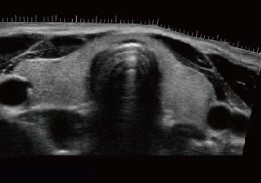

Примеры изображений:

Эластография позволяет оценивать плотность и эластичность тканей в реальном времени, что особенно важно при исследовании печени и молочных желез.